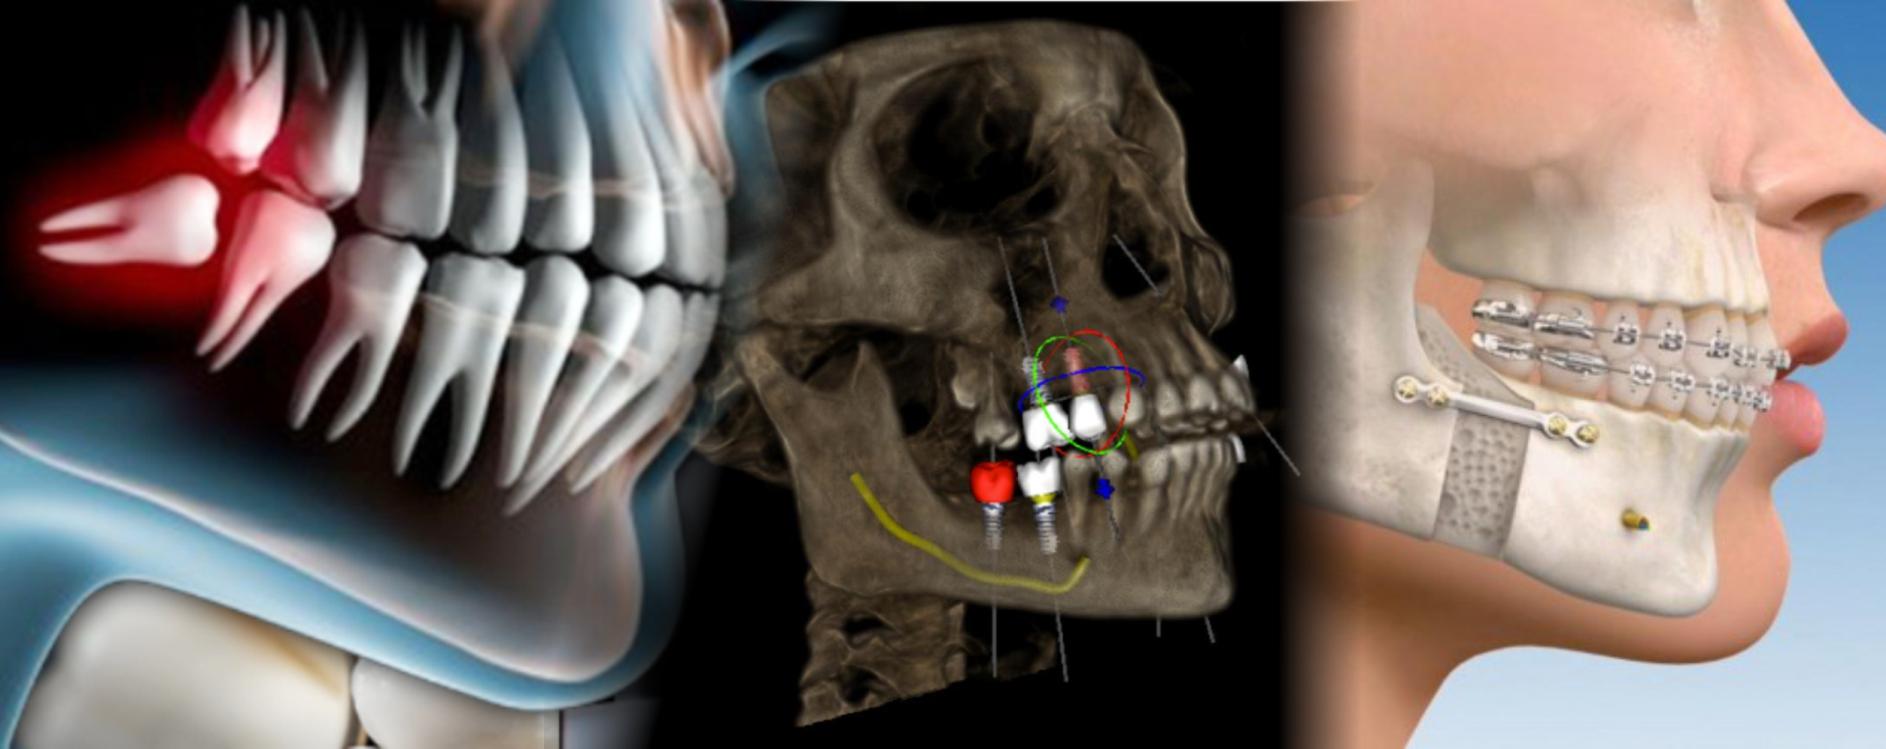

Cirugía Oral y Maxilofacial

Implantes Dentales

Ced. Espec. 7130382 UNAM

Trauma facial

Corrección de Maxilares

(cirugía ortognática)

Cirugía terceros molares

Patologías de maxilares